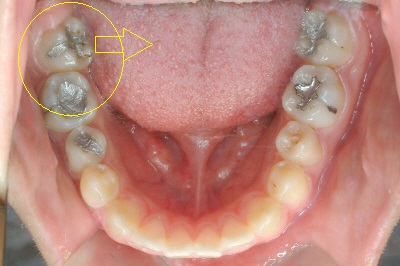

을 주소로 내원하신 20대 여성분인데 환자분의 오른쪽 어금니 교합은 아래 송곳니가 살짝 튀어나온 부분을 제외하면 어느 정도 괜찮을 것 같습니다.그런데 반대쪽 어금니를 보면 윗니에 가려져 아랫니가 거의 보이지 않는 상태에서 아랫니 어금니가 혀 쪽으로 넘어지면서 윗니 아랫니가 전혀 맞물리지 않는 상태입니다.가위교합(scissors bite)이라고 하는데 윗니는 뺨 쪽으로, 아랫니는 혀 쪽으로 완전히 엇갈린 교합의 양상이며, 이 교합은 시간이 지남에 따라 점점 심각해집니다.따라서 오랜 시간이 지나면 상하 어금니 치주(치경)가 나빠지고 어금니 전체를 발치하는 경우도 흔합니다.또한 정면 사진에서 위쪽 화살표를 보면 좋지 않은 교합 때문에 잇몸 마모증(Cervical abfraction)도 있습니다.

윗니 어금니가 뺨 쪽으로 많이 어긋난 상태입니다.치아가 조금씩 구부러져 있는 부분은 가위의 교합 교정을 하는 과정에서 자연스럽게 정돈된다고 생각됩니다.(교정치료를 치아를 다듬는 것으로만 생각할 수 있지만, 삐끗한 부분이 정돈되는 과정이 가장 쉽고 빠르게 중요한 것은 상하교합을 기능적으로 정상화하는 것입니다.)) 직업상의 이유로 장치를 부착할 수 없어 제거해야 하는 기간이 일시적으로 있었음에도 약 1년 정도의 기간으로 가짜 교합을 정상 교합에 맞추면서 치료를 종결하였습니다.